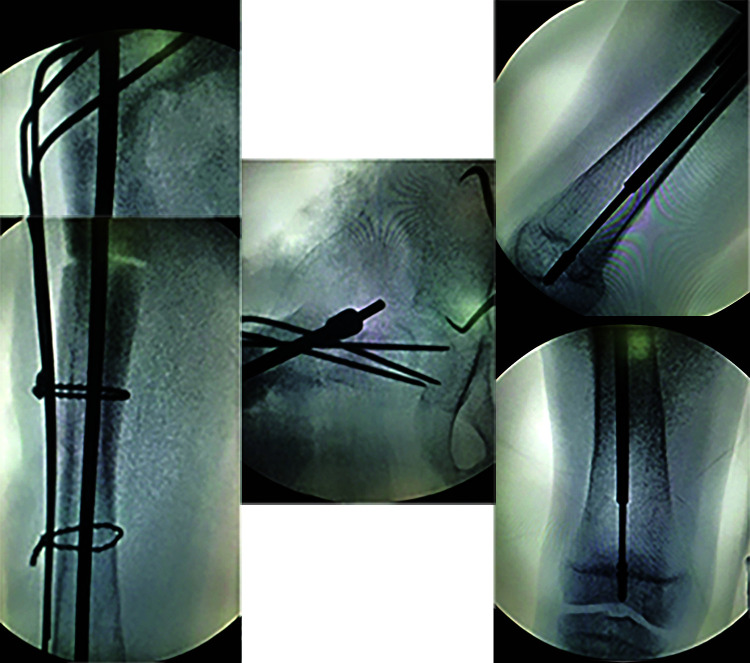

Osteogenesis imperfecta (OI) patients usually sustain repeated fractures from trivial trauma and also have skeletal deformities that affect walking. The bone fragility and repeated fractures produce deformities of the long bones especially in femur and tibia. However, neck of femur (NOF) fractures in OI are rarely described. A 11-year-old male patient known to have OI (Sillence type IV) sustained a NOF fracture after a fall. He also had proximal femoral anterolateral bowing proximally and over an intramedullary (IM) rod inserted 4 years back. He was treated by corrective osteotomy and stabilisation with an IM telescoping nail for the deformed femur and the Wagner technique for the NOF fracture. One year after operation, the patient had recovered satisfactory functional outcome with union of the NOF fracture and correction of the femoral deformity.

Conclusion: The method of the Wagner technique can achieve stable fixation for femoral neck fractures and introduces the least interference with concurrent telescoping nail insertion.